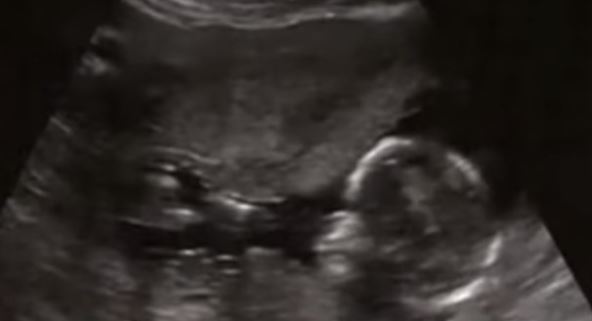

Foto: Printscreen Youtube / Sher Fertility Institute